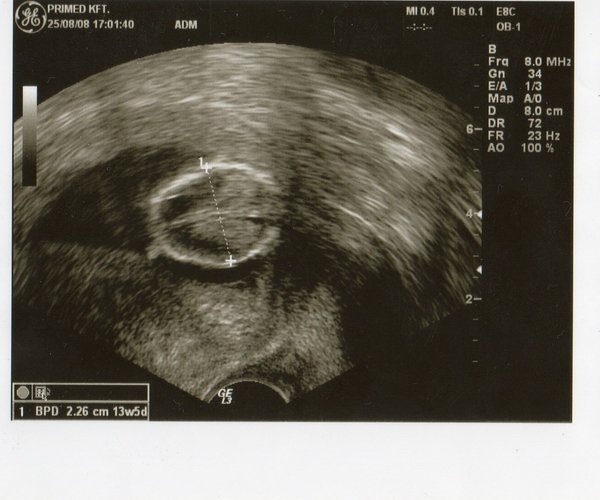

1. UH kép

1. UH kép

II. ultrahang